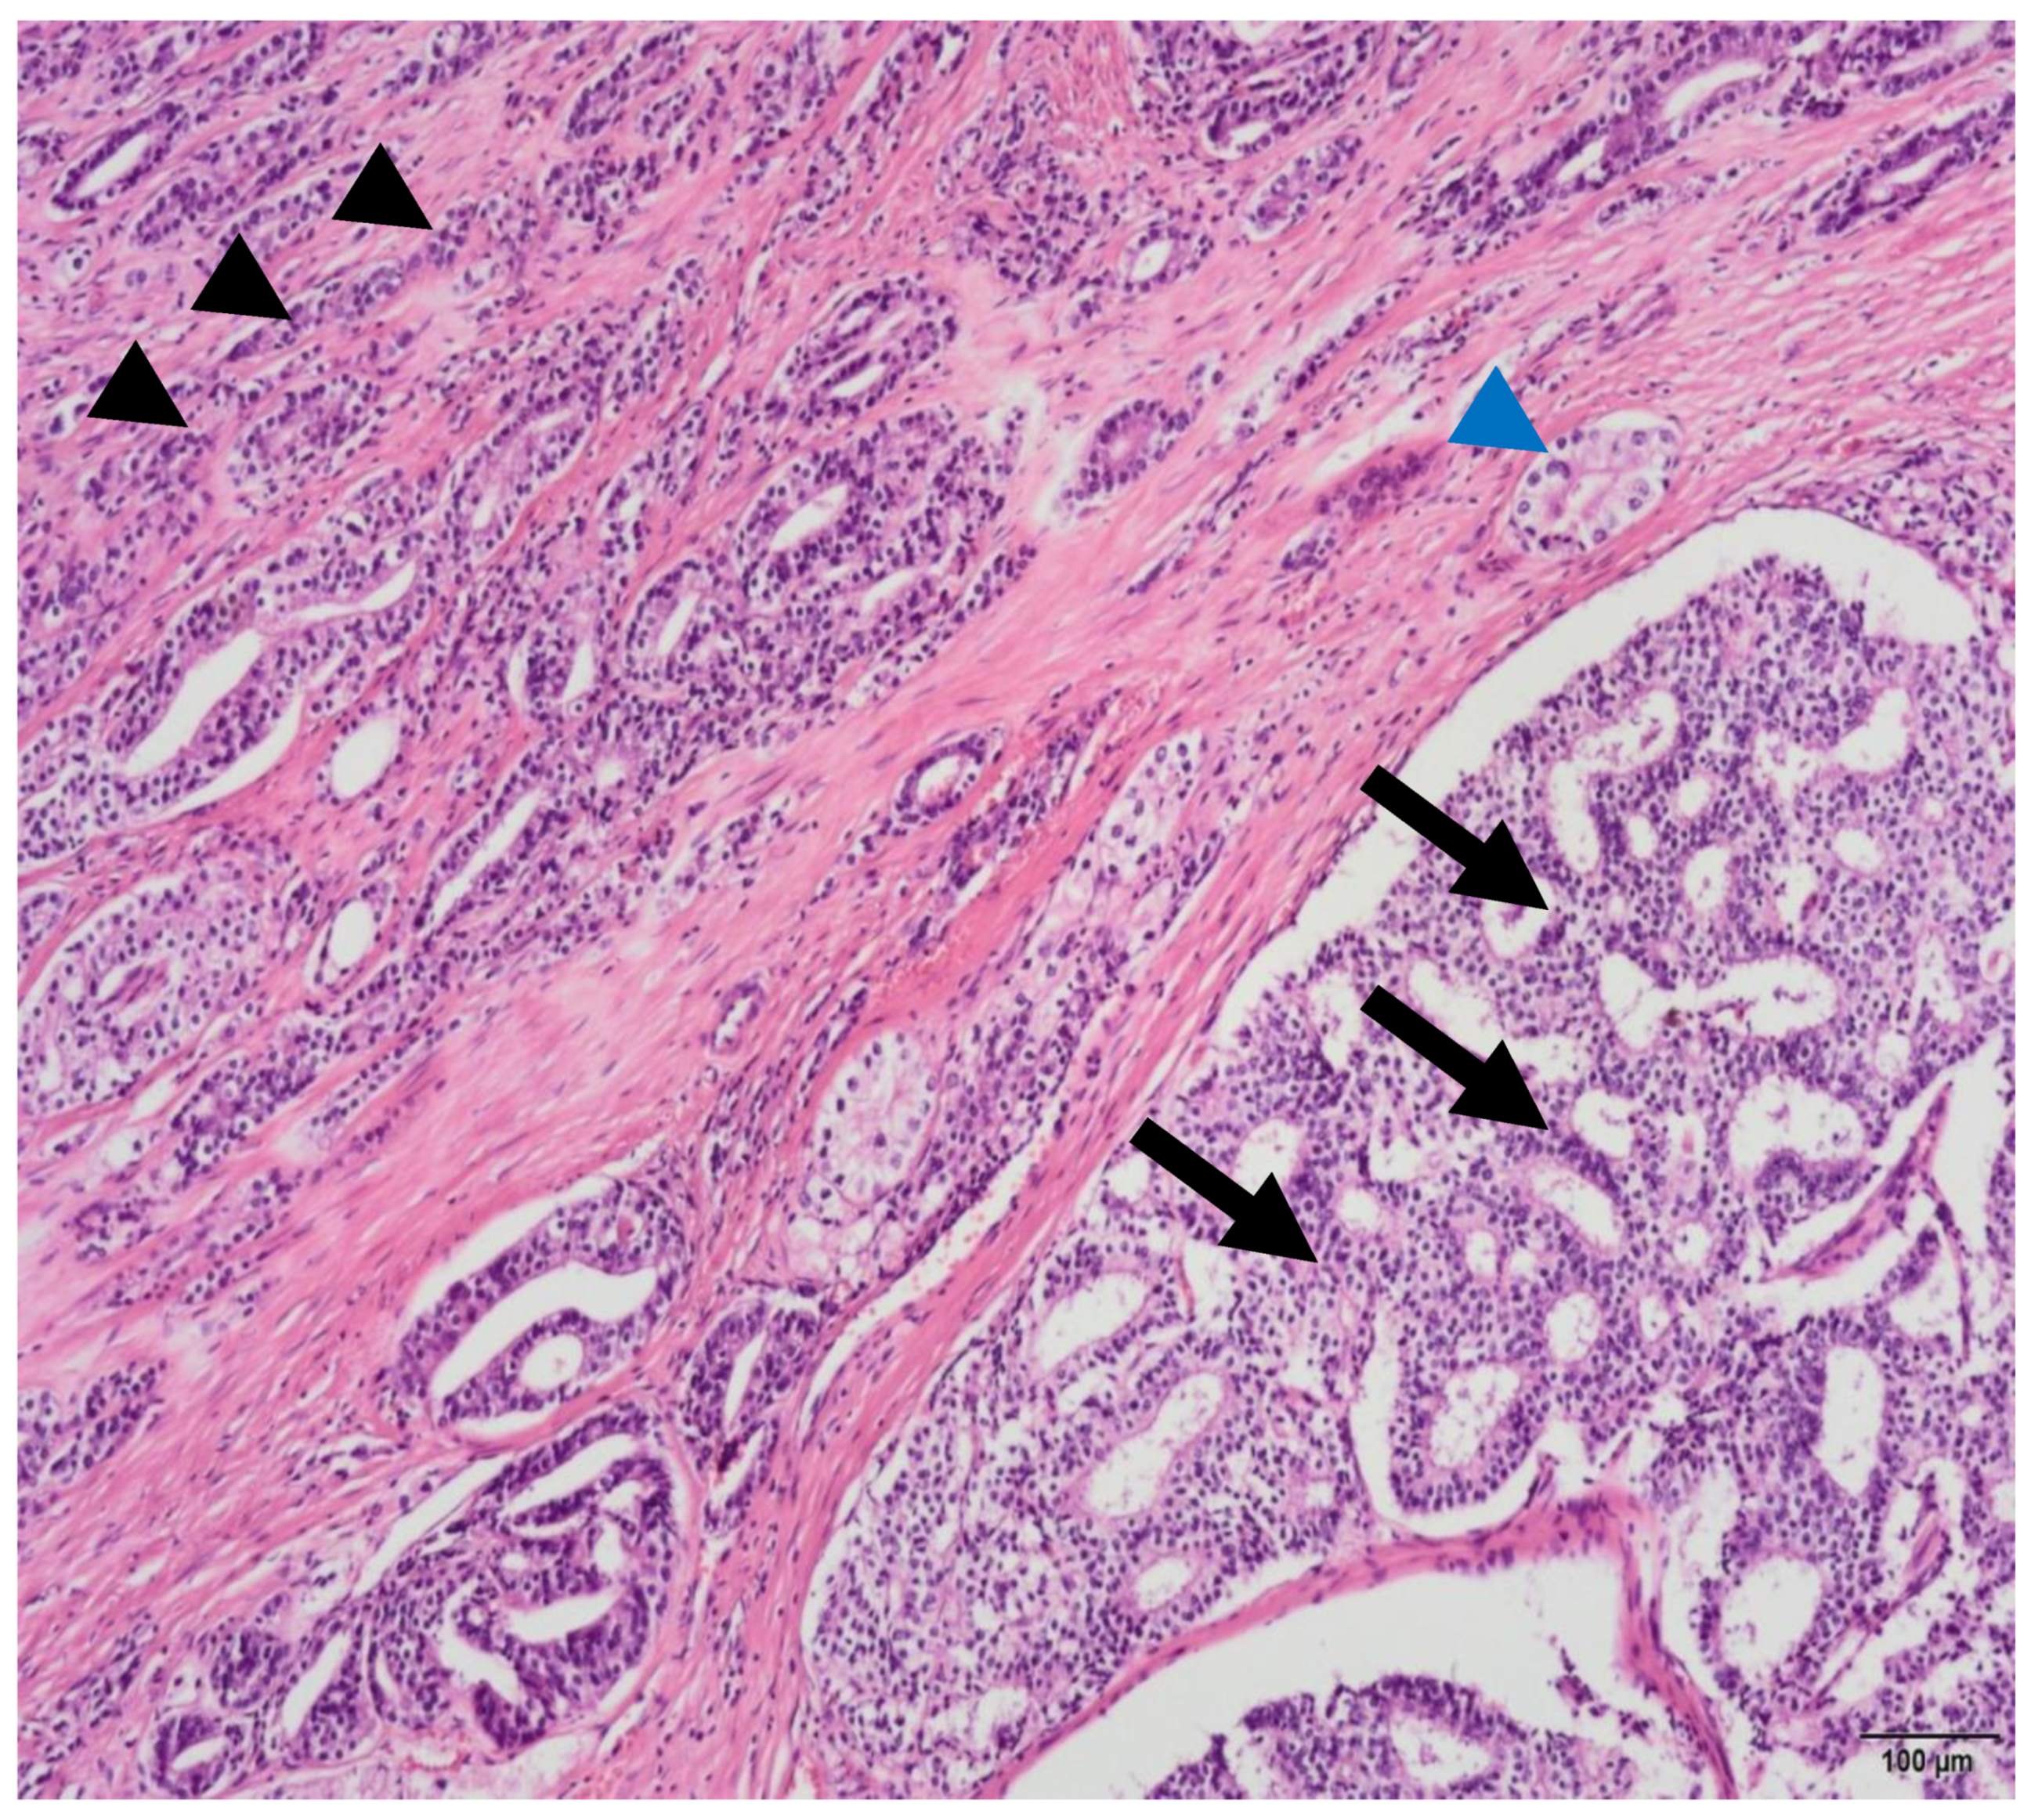

Figure 4.

Photomicrograph of a prostatic acinar adenocarcinoma with multiple morphological patterns, such as some uniform medium sized glands (blue arrowhead), small poorly-formed and fused glands (black arrowhead) and both large and small round cribriform glands (arrows) with well-formed lumina (H&E, 10×). Image provided by João Pimentel MD, Pathology Department, Centro Hospitalar e Universitário Lisboa Central, October 2021.